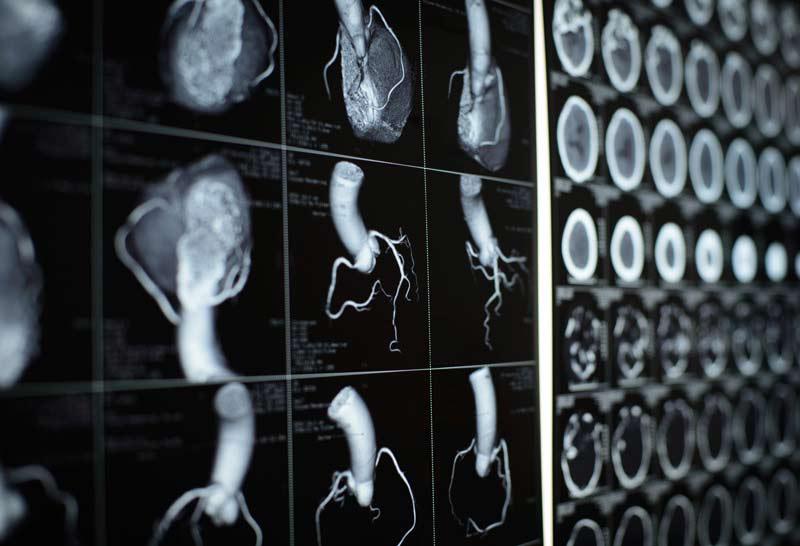

A cardiac computed tomography (CT ) scan uses many X-rays from different angles to construct images of your heart using a scanner and computer. This quick but detailed and high-resolution scan shows your healthcare provider problems with your heart structure, valves, arteries, aorta and more.

A cardiac computed tomography (CT) scan is a procedure that utilizes multiple X-ray beams from different angles to acquire high-quality, three-dimensional (3D) images of your heart, along with your great vessels and surrounding structures.

Cardiac CT uses advanced CT technology, with or without intravenous (IV) contrast (dye) to better visualize your heart structure and associated blood vessels. With multi-slice scanning, your healthcare provider can get high-resolution, 3D images of your moving heart and great vessels.

What does a CT scan of the heart show?

Your healthcare provider will be able to see your:

- Coronary arteries that supply your heart.

- Heart chambers, muscle and valves.

- Pulmonary veins.

- Thoracic aorta, and sometimes abdominal aorta.

- Sac around your heart (pericardium).